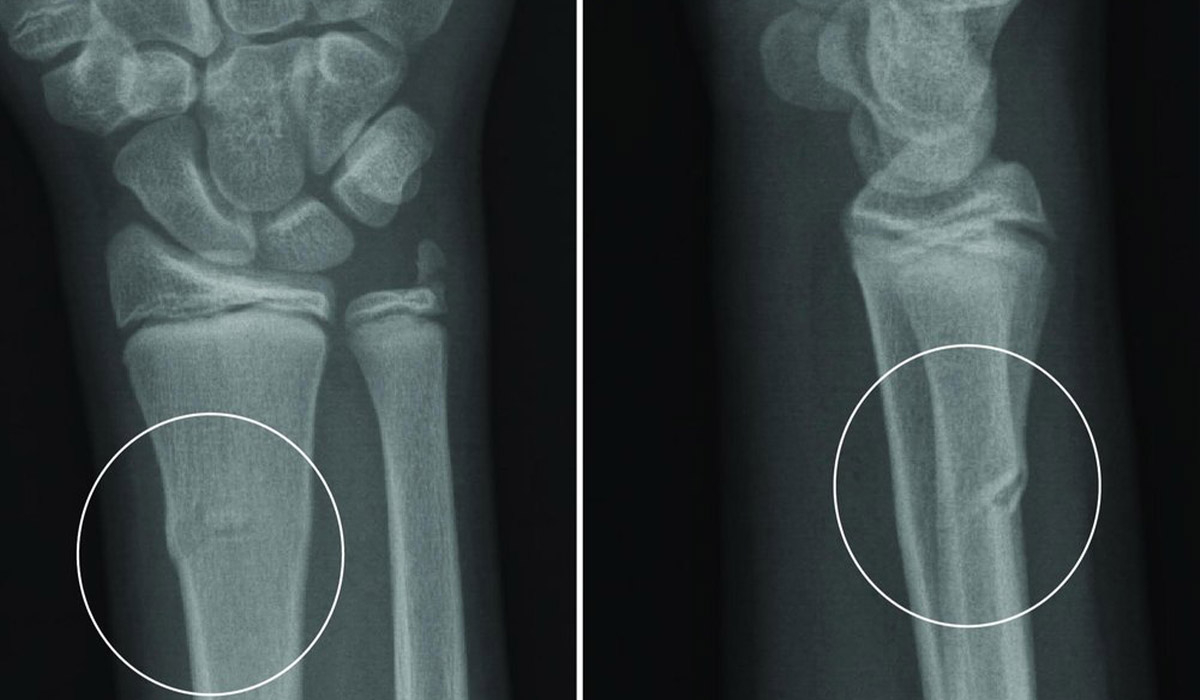

Діагноз необхідно підтвердити з допомогою рентгену. Діагностика також визначає наявність зсувів та осколків.

Основні типи переломів променевої кістки:

- Відкритий;

- Зі зміщенням;

- Осколковий (коли кістка роздроблена на осколки);

- Внутрішньосуглобний (коли травма зачіпає променезап’ястковий суглоб);

- Позасуглобовий